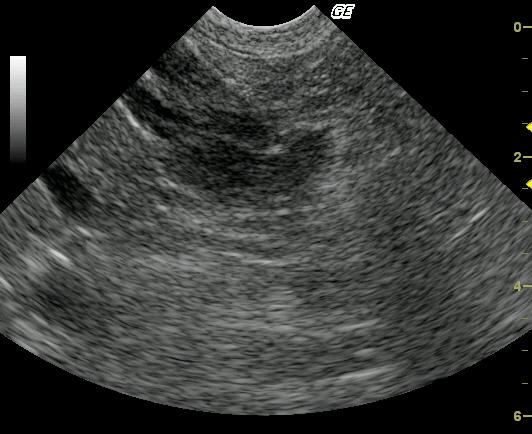

This 10 year old neutered male Beagle cross was presented for altered behavior. The physical exam was normal. CBC was normal while the blood chemistry revealed moderately elevated SAP and a slightly elevated total protein and slightly elevated globulin. The urinalysis revealed USG of 1.021 and 4+ proteinuria with inactive sediment. ACTH stimulation test was normal.